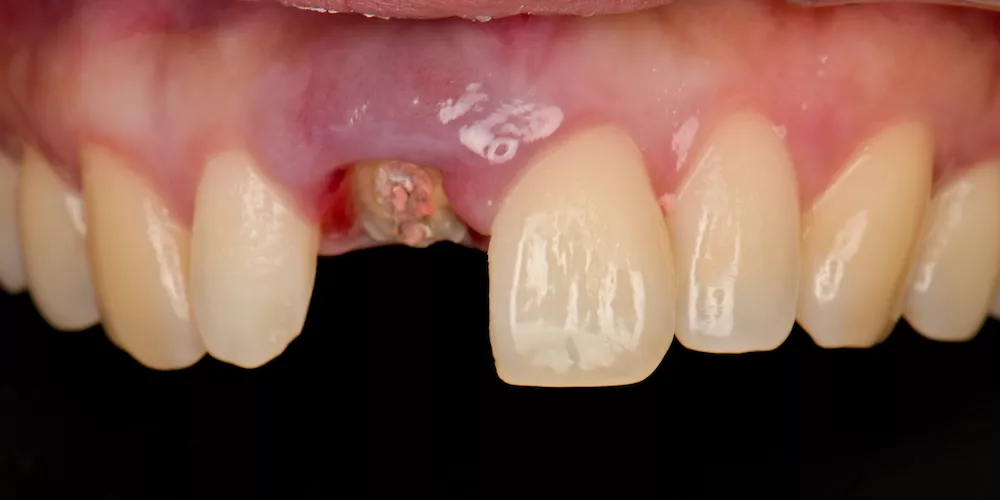

走進醫療領域越深,越能明白:「真正好的治療,從來不是只處理眼前的問題,而是要看見未來。」我需要在一顆牙齒背後,看見長遠的生活樣貌。

因此,每一次的治療,我都傾注最大的心力,在品質及細節上堅守高標準,讓成果真正經得起考驗。